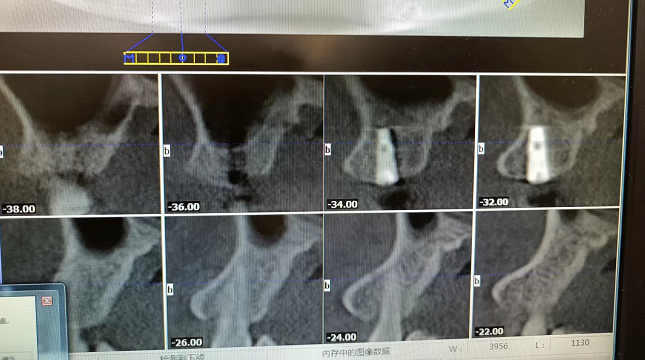

经过和患者的沟通和思索后,凭借着多年的口腔种植的经验,邢主任决定用侧压提升的方式来解决这个问题。即从牙槽嵴入路,采用种植定位,特殊钻头和方法提升上颌窦黏膜,并且提升后进行即刻种植,种植后获得了不错的效果,患者也很满意。如下图:

从种植后的口腔CT拍片可以看出,经过侧压提升种植后植体侧位、正位图都可以看出植体很直,成功种植后,下一步就等骨骼长成,5个月左右复查即可。